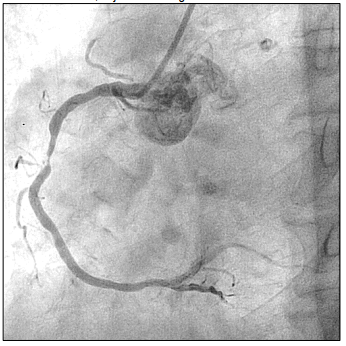

Paciente de 66 anos, relata queixa de dor torácica em aperto. Procura atendimento médico onde realiza ECG que evidencia IAM com supra de ST. Então, é levada à hemodinâmica onde é realizado o exame, cujo achado segue abaixo:

Em relação à anormalidade evidenciada, assinale a alternativa que apresenta a coronária acometida.